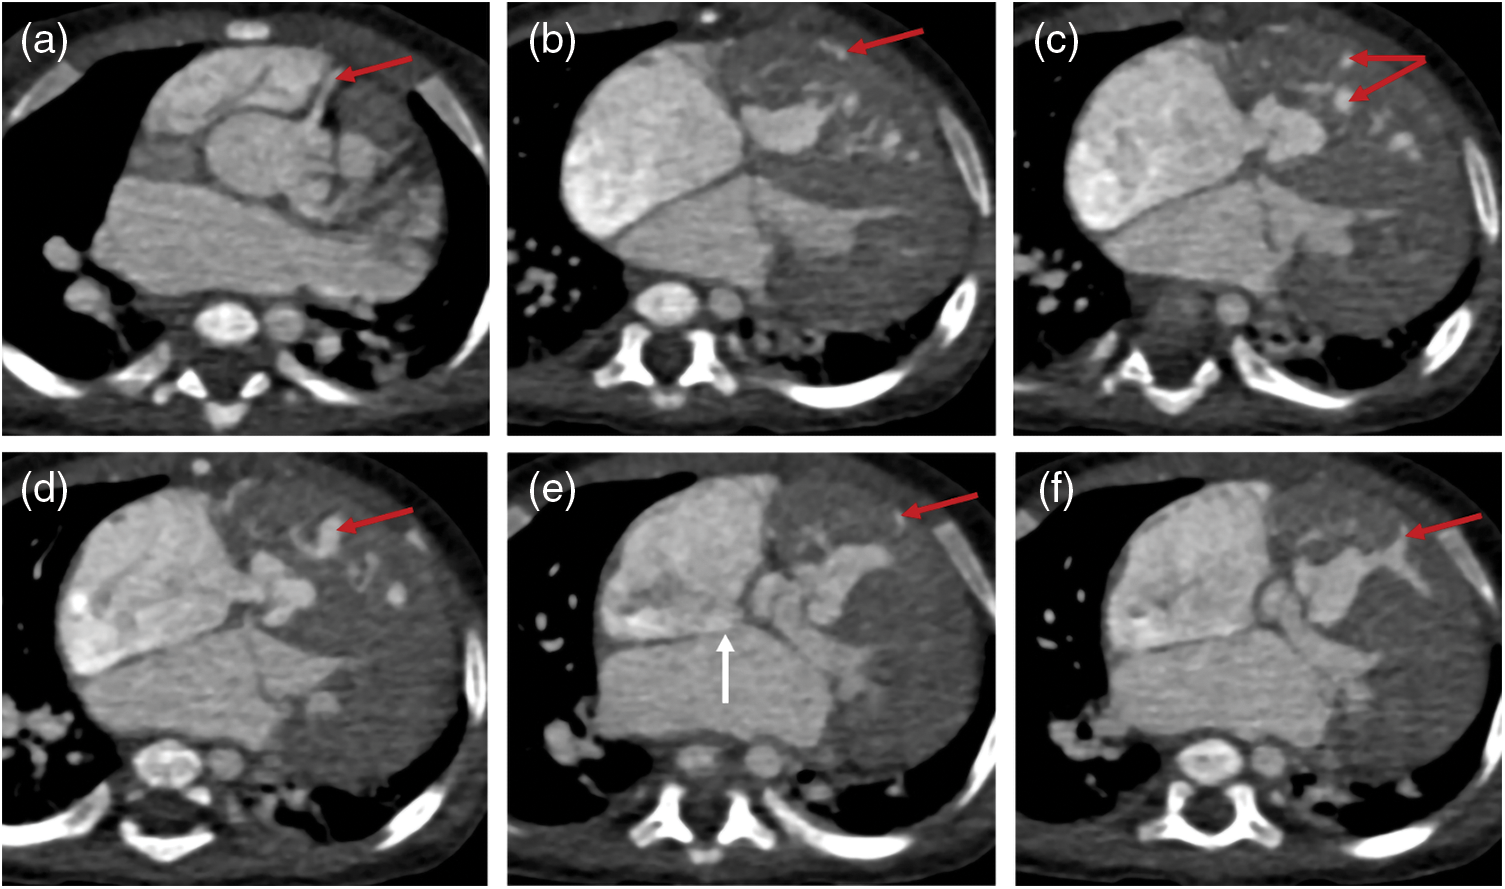

Figure 2: Two sets of images of a PA/VSD/MAPCAs patient. Images of (a–c) were captured in 2013 and (d–f) were taken in 2019. Unlike with the patient in Fig. 1, the blood supply of this patient lungs depended more on right coronary artery (CA, red arrows) than MAPCA (blue arrows). After six years, the right CA dilated more distinctly, while the left/right pulmonary artery (LPA/RPA, yellow arrows) and MAPCA changed little. (a–c): CA = 0.53 cm, MAPCA = 0.41 cm, LPA = 0.51 cm, RPA = 1.25 cm; (d–f): CA = 1.20 cm, MAPCA = 0.52 cm, LPA = 0.66 cm, RPA = 1.53 cm